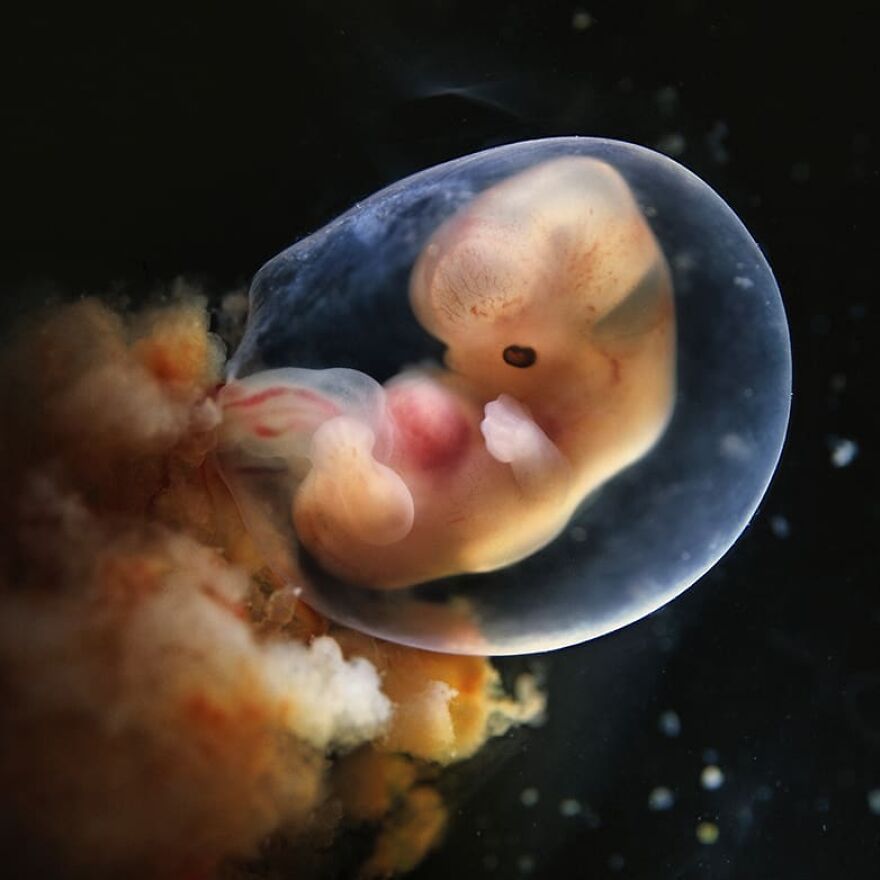

Embryo, 7 weeks, 1990

Embryo, 6 weeks, 1,5 cm

From the series "A Child is Born", 1965